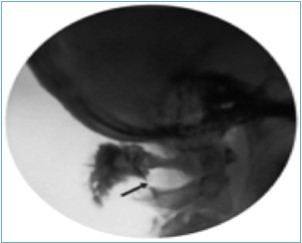

Figure 10.Lateral fluoroscopic image showing the final contrast spread; the arrow shows the outline of the greater occipital nerve at the level of the inferior oblique capitus muscle. Image Courtesy of Gabor Racz, MD

Because of the proximity to the vertebral artery and the potential risk of intravascular injection, few interventionalists have been interested in AA injections, and, since the proximal GON travels over the posterior arch of the atlas, even fewer have been interested in direct injections of the proximal GON. In an effort to avoid the “locked-in” syndrome complication seen with occipital injections, Dr. Gabor Racz developed a suboccipital approach to the suboccipital space in 1982, which has recently become more popular7, 8. A curved, bullet-tipped needle with side port injection, attached tubing, and wings (dubbed the “Stealth needle”™ because of its resemblance to the Stealth bomber) Figure 5 is used to approach the suboccipital triangle from above. Since the underlying pathology is usually bilateral, the procedure is usually performed bilaterally.The patient is positioned prone on the fluoroscopy table, with the neck in flexion; the hair is pulled cephalad, and the suboccipital area is sterilely prepped and draped. The inion and conjoined tendon are identified by palpation and the nuchal line is identified by fluoroscopy; the entry site should be 2cm lateral to the midline on the nuchal ridge. After making sure by palpation that the planned entry is not directly over the occipital artery, a small skin wheal of local anesthetic is injected via a 30g needle. Because the galea is so strong, an 18g needle is used to create a small stab incision in the scalp and deep fascia to facilitate the entry of the blunt-tipped needle. Standing at the head of the bed, the Stealth needle is held by the wings like a butterfly IV needle, and, with tip facing down and toward the feet Figure 6 the needle is advanced caudally. The needle position is initially identified on an anterior-posterior fluoroscopy view, with the target medial to the superior pars of C2 Figure 7 The needle is advanced through the muscle and fascial layers of the trapezius and semispinatus with confirmation of location on lateral view, aiming for the superior lamina of C2 at the level of the spinous processes Figure 8. Contrast is injected to verify needle placement Figure 9 followed by 10 cc of local anesthetics and steroids (4.5ccs 0.2% ropivicaine, 4.5ccs 1% lidocaine, and 10mg of dexamethasone on each side) to perform an adhesiolysis, freeing up the greater occipital nerves Figure 10 Because this technique is usually performed bilaterally, lower concentrations of local anesthetic are used to avoid toxicity issues.